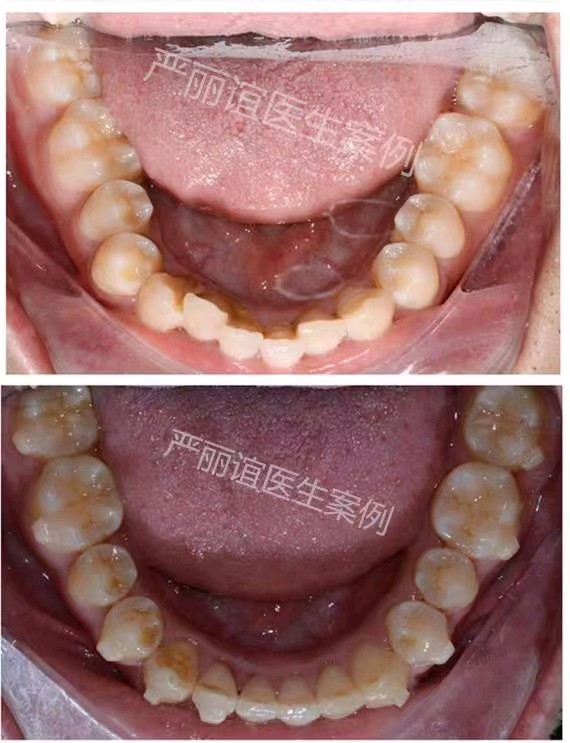

患者:成年男性

主诉:微笑时门牙有缝影响美观,要求矫正。

结果:牙性前突    深覆合II    深覆盖II

矫正方案:不拔牙矫正,下颌前牙少量片切,排齐整平上下颌牙齿,压低下颌前牙,内收上颌前牙,关闭上颌牙缝。

矫正时间:1.5年。